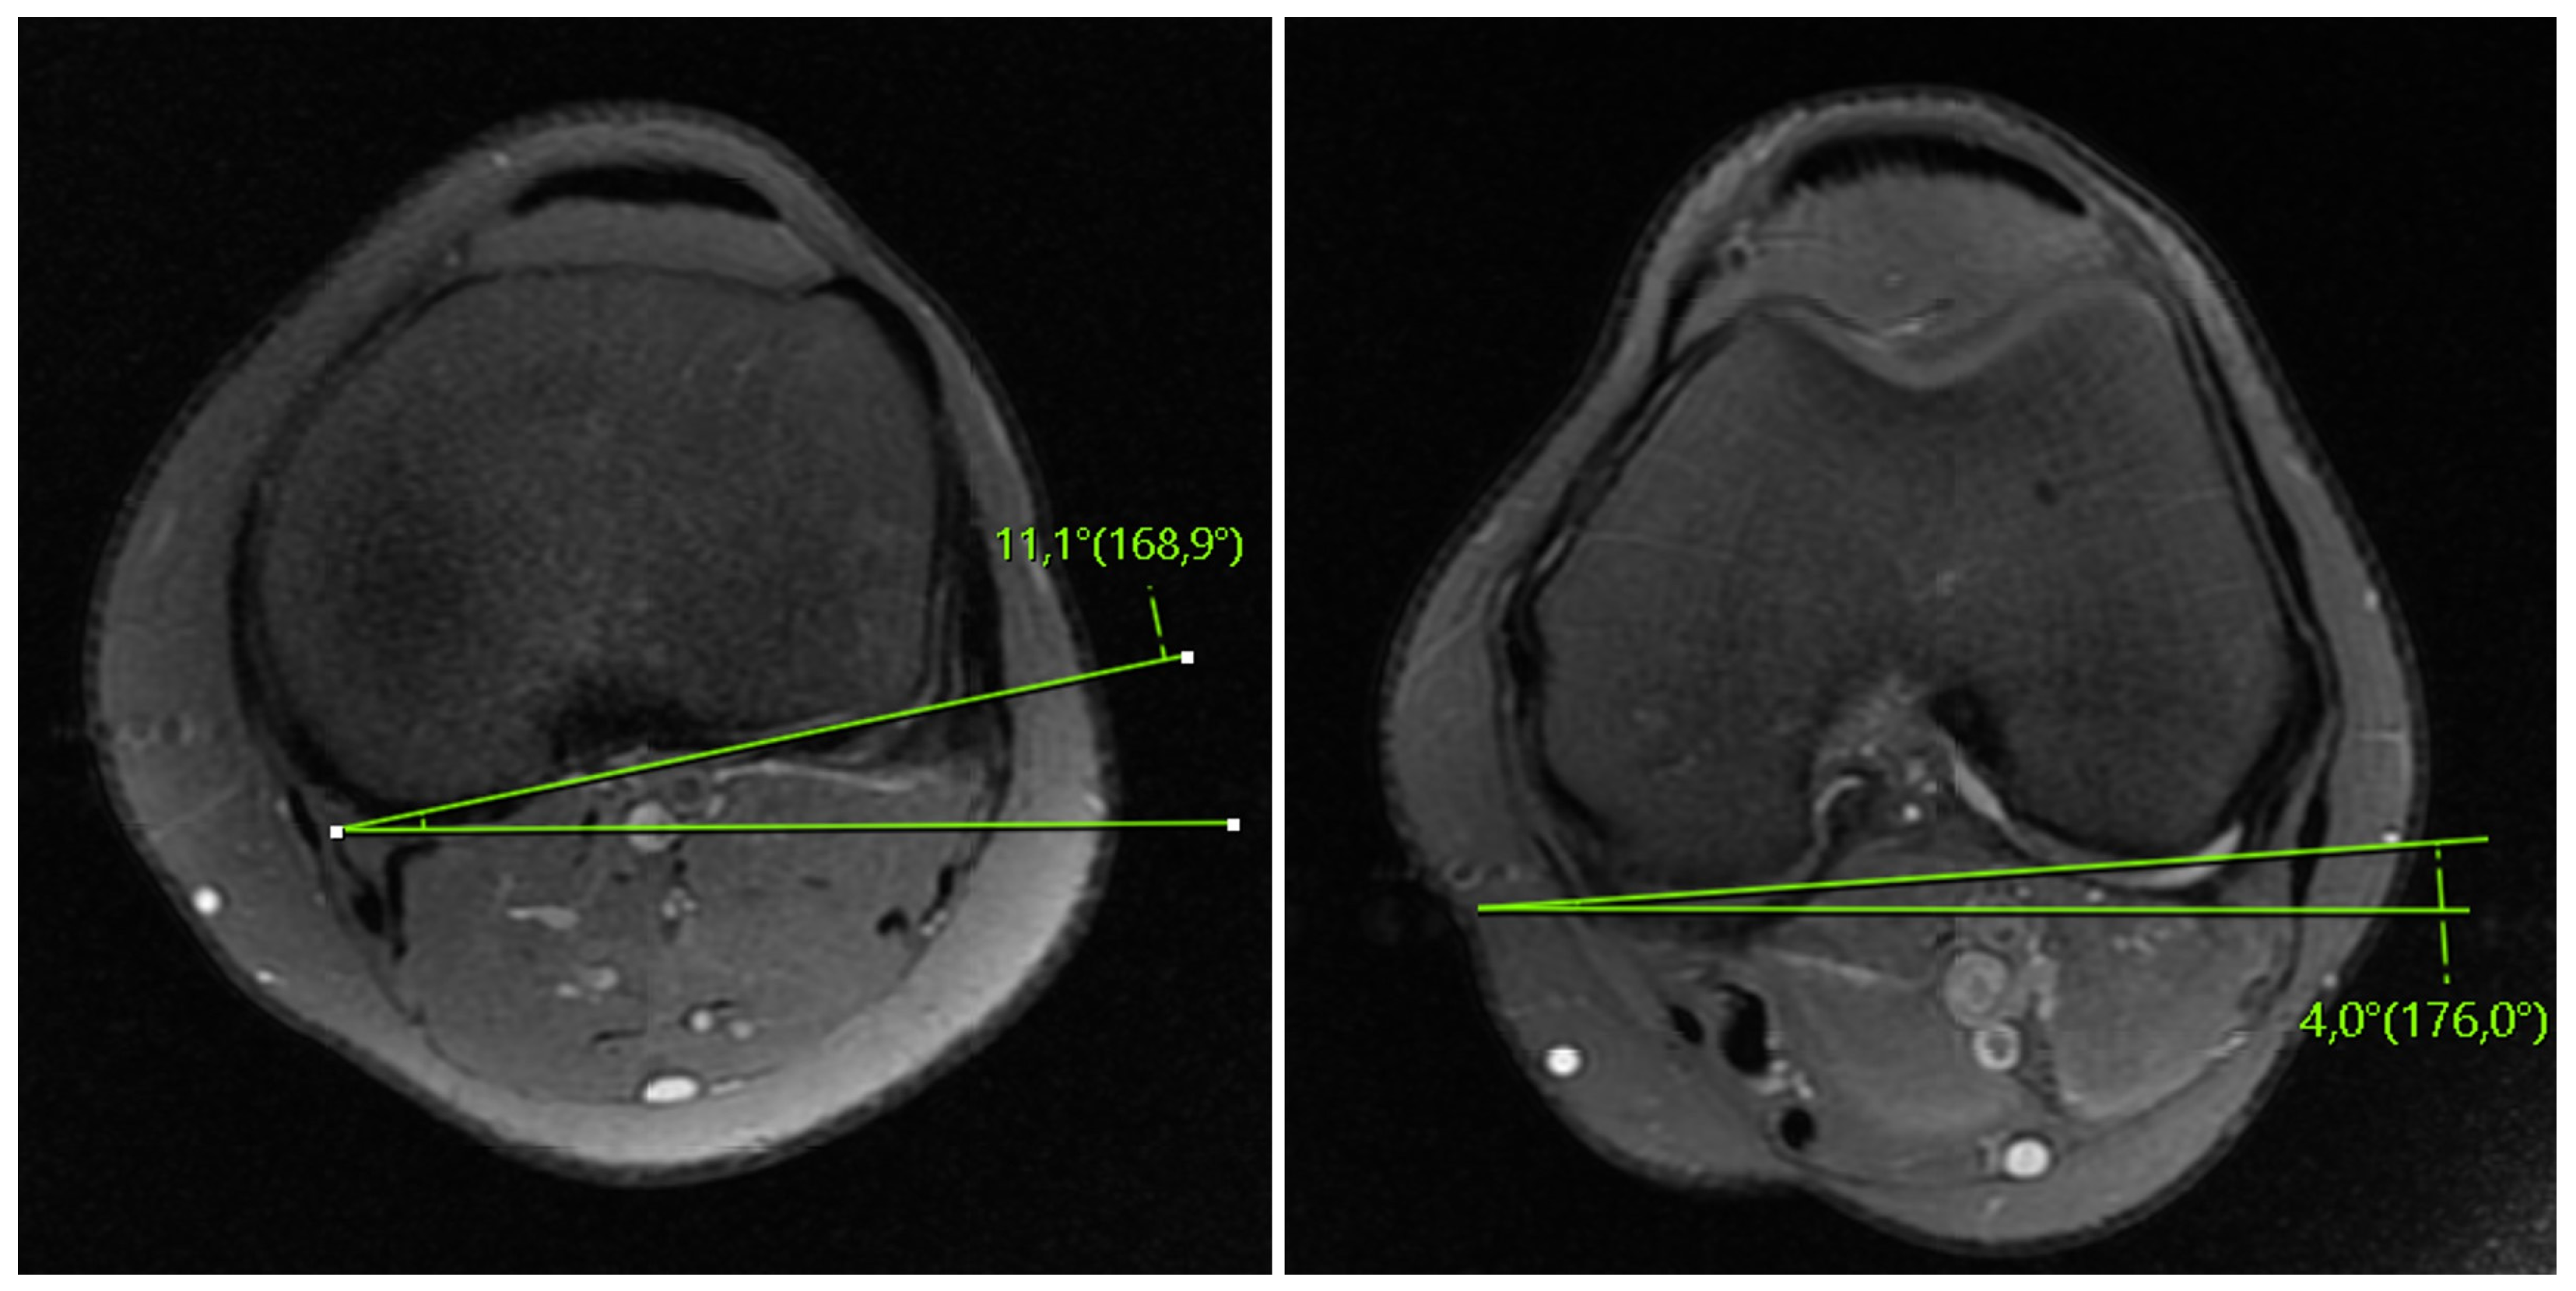

- Vassalou, E.E.; Klontzas, M.E.; Kouvidis, G.K.; Matalliotaki, P.I.; Karantanas, A.H. Rotational Knee Laxity in Anterior Cruciate Ligament Deficiency: An Additional Secondary Sign on MRI. Am. J. Roentgenol. 2016, 206, 151–154. [Google Scholar] [CrossRef] [PubMed]

- Hong, C.-K.; Hoshino, Y.; Watanabe, S.; Nagai, K.; Matsushita, T.; Su, W.-R.; Kuroda, R. The Coronal Lateral Collateral Ligament Sign in the Anterior Cruciate Ligament-Injured Knees Was Observed Regardless of the Knee Laxity Based on the Quantitative Measurements. Knee Surg. Sport. Traumatol. Arthrosc. 2022, 30, 3508–3514. [Google Scholar] [CrossRef]